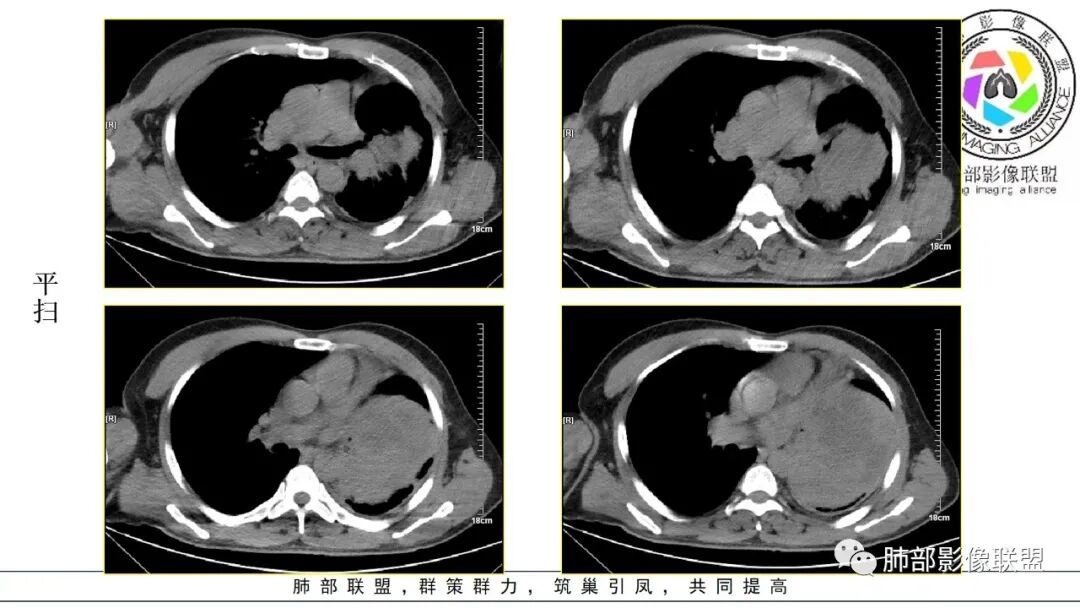

左侧胸腔巨大软组织肿块,边缘膨隆、清晰,临近血管及气管受压推移,肿块内密度不均匀,见大片状坏死及条形钙化,增强后不均匀强化,考虑恶性,定位肺内,肉瘤样癌可能大,定位肺外,纵隔来源恶性鞘瘤,胸膜来源sft

成年人,左肺巨大肿块,气管,支气管受压闭塞及被推挤,病灶内有坏死和钙化,增强病灶明显不均匀强化,考虑外向内生长的恶性病变,肉瘤样癌,癌肉瘤,滑膜肉瘤,平滑肌肉瘤等

中年男性,间断性发热3天,肿瘤指标增高,左肺巨大形肿块,平扫密度不均,内可见片状液化坏死区及钙化,邻近下叶支气管堵塞,增强不均匀强化,实性区明显强化,考虑恶性,肺内肉瘤、胸膜来源恶性SFT,NSE明显高,大神泌?

3.病灶密度不均,轻度强化,坏死或液化范围甚大,边界可分辨,部分“壁”可见钙化。

1.无论是肺部还是胸腔“巨大实性密度”块影且边界较清楚者,较少为上皮来源的肺恶性肿瘤,而更符合间叶组织来源的肉瘤。

尤其是病程较长(纵隔移位明显),相对破坏力不强,缺乏远处转移证据的,表明其恶性程度并不那么高。